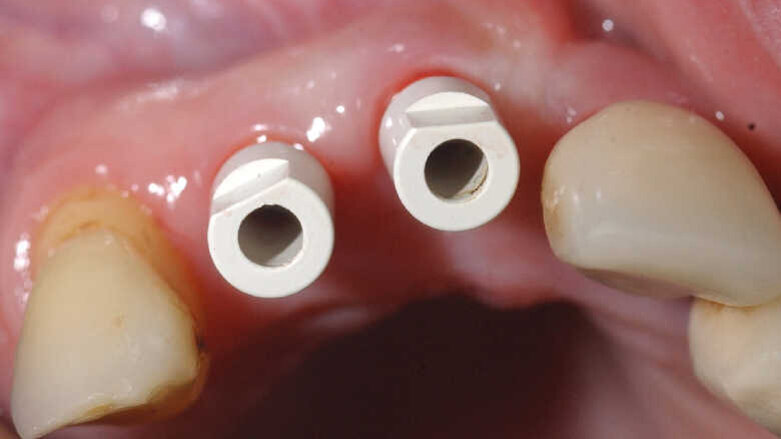

Figs. 11a & b : Vues cliniques et occlusales des scan bodies en place. Notez les positions et les axes obtenus, qui faciliteront les réalisations prothétiques définitives.

Fig. 12 : Radiographie de contrôle objectivant le bon enfoncement des scan bodies.

Des scan bodies (Core 3D), correspondant aux implants, sont positionnés et les empreintes optiques réalisées avec la camera 3Shape (Figs. 11a et b). A ce stade, il est fortement recommandé de faire une radiographie de contrôle, afin de vérifier le bon enfoncement des scan bodies et pour éviter toute erreur, qui se répercuterait au niveau de la prothèse (Fig. 12).